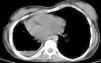

Chronic changes like fibrodestruction, calcified parenchyma, volume loss, and pleural thickening were significantly more common in MDR-TB group (Fig. 1).